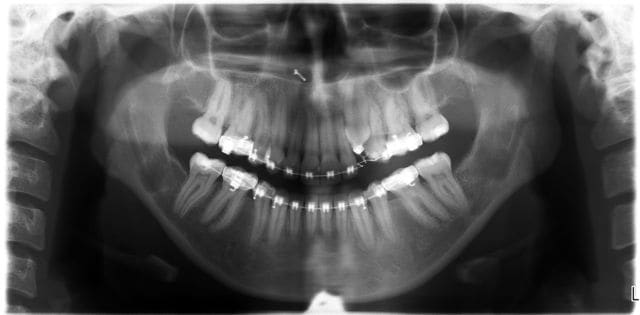

jeune fille pour une désinclusion de 23, 10 ans sur la carte vitale, dentition en avance pour son age

sur la pano j'étais parti pour 2 surnuméraires

Sinon c'est un odontome composé ton truc = tumeur odontogène

Sans doute hormis les deux surnumerairaires tout était dans un sac, mais comme, je ne m'y attendais pas je ne peux pas dire s'il était fermé ou ouvert.